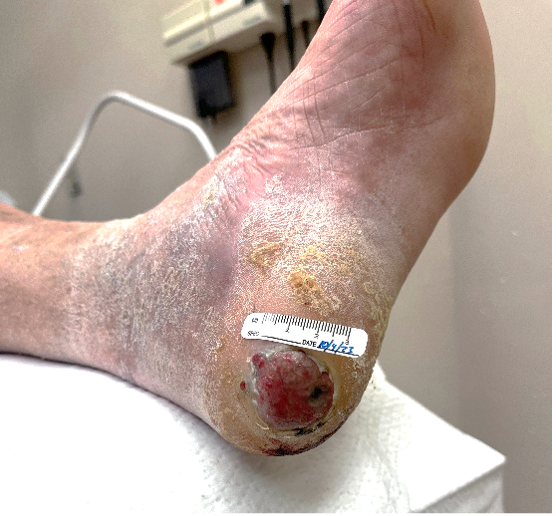

A 70-year-old Hispanic male with past medical history of alcohol dependence and idiopathic neuropathy presented with a chief complaint of chronic left heel ulcer. Physical examination revealed an irregularly bordered ulceration with a hypergranular wound base (Figure 2). Initial treatment included sharp debridement, silver-impregnated dressings, and an offloading shoe for wound healing. After months of nonhealing with standard of care, a 4-mm punch biopsy confirmed an invasive acral melanoma.